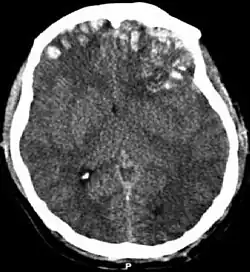

CT scan showing cerebral contusions, hemorrhage within the hemispheres, subdural hematoma on the left, and skull fractures[1]